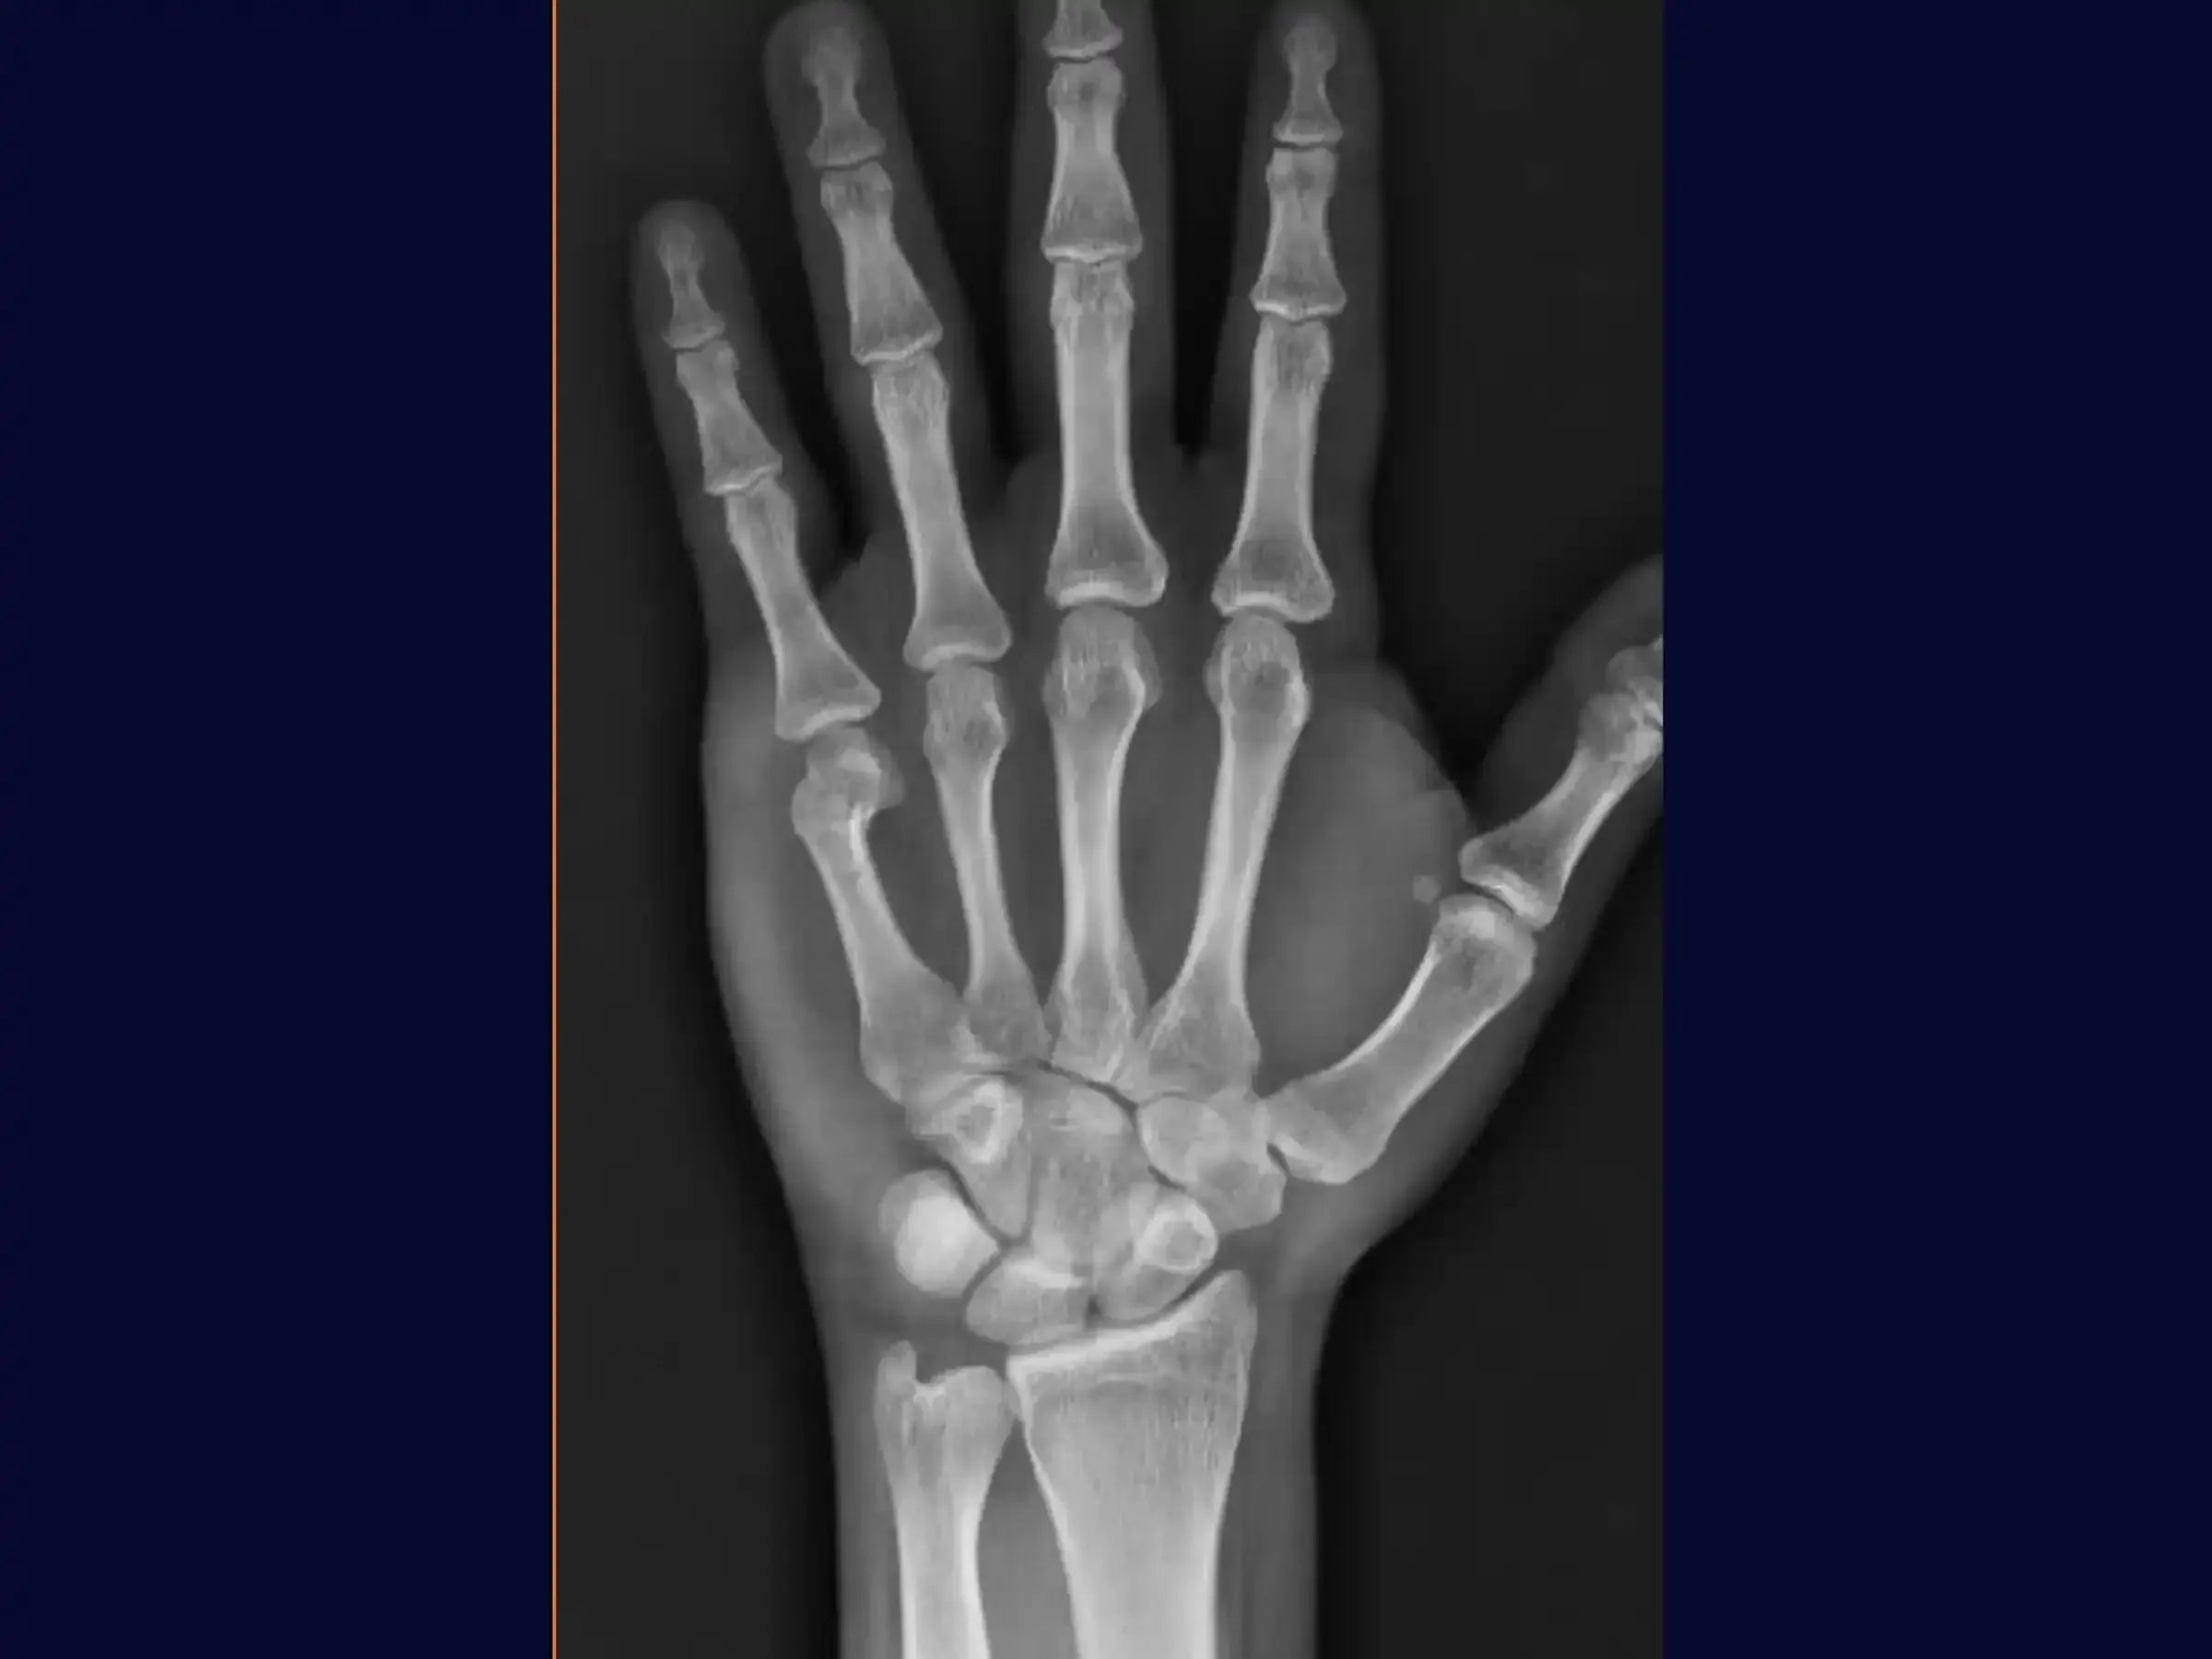

- Planificación preoperatoria basada en radiografías.

- Evaluación radiográfica y planificación precisa: Aprenda a interpretar radiografías para identificar indicaciones quirúrgicas. Domine las marcas preoperatorias con un bolígrafo dermográfico, alineándolas con la diáfisis del quinto metacarpiano en las proyecciones anteroposterior (AP) y lateral para guiar la guía.